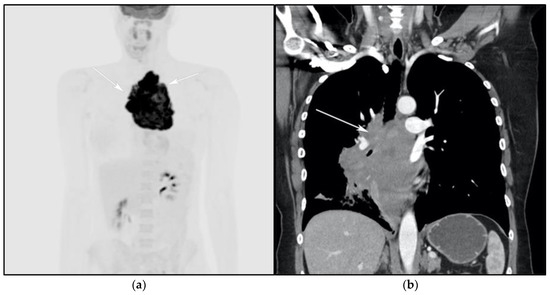

The differential diagnosis of PMLBCL includes other anterior mediastinal masses such as CHL, germ cell tumors, and large thymic tumors, which can display necrosis and calcifications on CT [32]. Differentiation between PMBCL and CHL is not possible based on imaging findings alone. More aggressive clinical behavior such as superior vena cava syndrome may help distinguish PMBCL from CHL [33] (Figure 5).

Figure 5.

A 24-year-old female presenting with cough and dyspnea with plethora of the face. (a) Maximal intensity projection (MIP) FDG PET/CT shows hypermetabolic anterior mediastinal mass (white arrows) with no other sites of disease involvement in the body. (b) Coronal contrast-enhanced CT image shows significant vascular and airway compromise by an ill-defined anterior mediastinal mass (white arrow). Biopsy-proven primary mediastinal B-cell lymphoma. Main differential diagnosis would be Hodgkin’s lymphoma. However, unlike in Hodgkin’s lymphoma, primary mediastinal B-cell lymphoma often shows frequent invasion of the mediastinal vessels, frequently resulting in superior vena cava syndrome.

The use of 18F-FDG PET/CT is essential in the evaluation of patients with PMLBCL to reveal sites of disease not visible on CT and to provide more accurate staging and radiation field planning (Figure 6). 18F-FDG PET/CT may also be beneficial for restaging after chemotherapy and/or radiotherapy, or when relapse is suspected [34]. Negative 18F-FDG PET/CT after two or four cycles of chemotherapy has a negative predictive value and may predict excellent outcome in patients, achieving complete response without relapse. Patients who have residual activity equal to or higher than liver activity after immunochemotherapy treatment are more likely to relapse. In such instances, the addition of radiotherapy to the treatment regimen should be considered to avoid relapse in those high-risk patients. Relapse usually occurs within 1 year and is more likely to be widespread, involving distant extranodal sites such as the CNS, liver, kidneys, adrenal glands, GI tract, ovaries, and pancreas. Late relapses are very uncommon [35]. 18F-FDG PET/CT can also efficiently assess post-treatment response, differentiating between necrotic or fibrotic tissue and residual masses containing viable tumor [33,36]. There are various potential challenges to 18F-FDG PET/CT post-treatment implementation, including false-positive results secondary to thymic rebound hyperplasia, specifically seen in the young population. This can be limited by increasing the interval between treatment and imaging. Additionally, MRI can be helpful in those cases, and high signal on T1 in phase imaging with loss of signal on the out of phase sequences is consistent with thymic rebound hyperplasia (Figure 7 and Figure 8) [34,37].